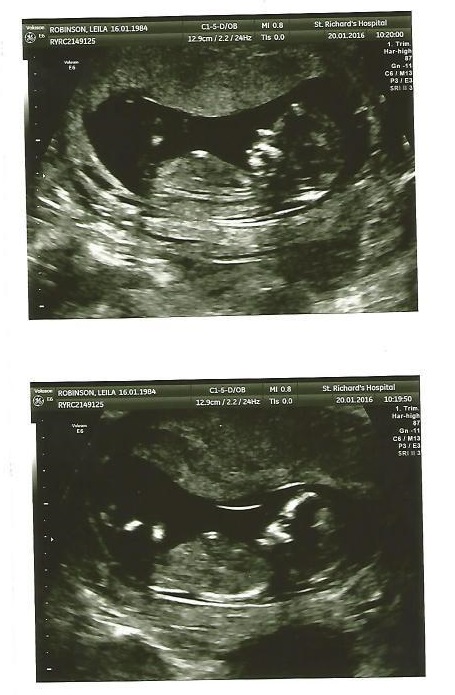

sorry , I'm new .hope you can see it now.it's just a bit odd.because it looks like if that's nub , is not in right place.

Hmm I'm not sure I'm seeing a nub but if you asked me to guess I would say girl since what I am seeing looks flat. This is a hard one though:/

I'm thinking girl from the 2nd pic... assuming that is the nub I can see.

I can't see it Purple. This really confused me now.I had 15 weeks four days scan. Doctor looked very quickly and told me he can see something between legs but can't see testicle.